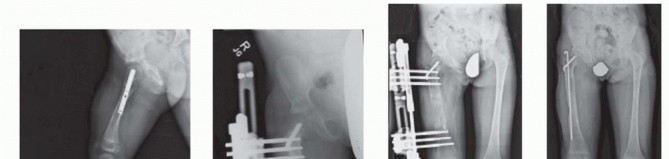

Prosthetic reconstruction surgery is recommended for most type 3 CFD due to the extensive deficiency present. This is especially the case for type 3b because there is a stiff knee joint (<45 degrees of motion). Although type 3a can be converted to type 2b, the treatment would consist of four or more lengthenings. Rotationplasty is recommended for most type 3a because it provides a more predictable functional result than does lengthening ( FIG 7 ).

releases that were addressed during a previous superhip or superknee procedure do not need to be repeated. Illustration 13 for Treatment for Congenital Femoral Deficiency: What You Need to Know Illustration 14 for Treatment for Congenital Femoral Deficiency: What You Need to Know Illustration 15 for Treatment for Congenital Femoral Deficiency: What You Need to Know FIG 7 • A. Patient with Paley type 3b CFD with severe leg length difference and knee flexion contracture. B. Clinical photo just prior to rotationplasty. C. Radiograph after Paley modified Brown rotationplasty. D. Photograph showing the appearance after rotationplasty. E,F. Side views showing knee flexed (ankle at neutral) and knee extended (ankle plantar flexed). _ Lengthening via External Fixators *_ Femoral lengthening with an external fixator can be performed with various devices. The essential principle of lengthening with external fixation is to stabilize the knee during lengthening while allowing for knee motion. This is accomplished by using hinges and external fixation of the tibia. From 1987 to 2000, the author used only the Ilizarov apparatus with fixation across the knee joint with a hinge for all CFD lengthening cases. This method has previously been described.9 A monolateral external fixator was not used because it could not articulate across the knee joint. From 2000 to 2009, the author modified the Orthofix Limb Reconstruction System (LRS) rail (Orthofix, Inc., McKinney, TX) with the Sheffield Ring Fixation System arch (Orthofix) to articulate across the knee with fixation to the tibia. This method was used for all CFD cases between January 2000 and May 2009. From 2009 to the present, the author designed a special external fixator specifically for articulated spanning of the hip and knee joints. The Modular Rail System (Smith & Nephew, Memphis, TN) has been used in all CFD cases since June 1, 2009.

Because of the correction of the abduction contracture and the opening wedge of the Dega, it is not possible to close the apophysis. The apophysis is pulled up and the level marked with a pen. The crest is then resected using a saw until the medial and lateral apophysis can be repaired without excessive tension ( TECH FIG 3C,D ). This is called the abductor slide technique . The TFL is then sutured to the rectus femoris ( TECH FIG 3E ). The incision is closed in layers. A suction drain is used and is left in place until the drainage stops (<10 mL per 24 hours), which can take several days. Prophylactic antibiotics are administered intravenously until the drain is removed. Illustration 30 for Treatment for Congenital Femoral Deficiency: What You Need to Know Illustration 31 for Treatment for Congenital Femoral Deficiency: What You Need to Know Illustration 32 for Treatment for Congenital Femoral Deficiency: What You Need to Know TECH FIG 4 • A,B. CFD Paley type 1b with delayed ossification of femoral neck. C. Superhip procedure at age 2 years including insertion of BMP in femoral neck. D. The neck is fully ossified by age 3 years. E,F. First lengthening is performed at age 4 years with Smith & Nephew Modular Rail System external fixator with articulation across the knee joint. G. Eight centimeters of lengthening is achieved. H. Removal of external fixator with Rush rodding of bone to prevent fracture. A spica cast is applied with the hip in full extension, neutral abduction, and neutral rotation. The knee is splinted in full extension. The cast is bivalve to allow for swelling. One week after surgery, the cast is made removable and gentle flexion and extension ROM of the hip and knee started. TECH FIGS 4 and 5 are two case examples of superhip procedures. *

Illustration 33 for Treatment for Congenital Femoral Deficiency: What You Need to Know Illustration 34 for Treatment for Congenital Femoral Deficiency: What You Need to Know TECH FIG 5 • A. Two-year-old girl with CFD Paley type 1b with delayed ossification and severe angulation of the subtrochanteric level of the femur. B. The deformity is fully corrected, and the femur is healed after the superhip surgery. C. Lengthening of the femur was performed at age 4 years. D,E. X-rays after lengthening of the femur 7 cm and insertion of Rush rod. 1. # Superknee Procedure